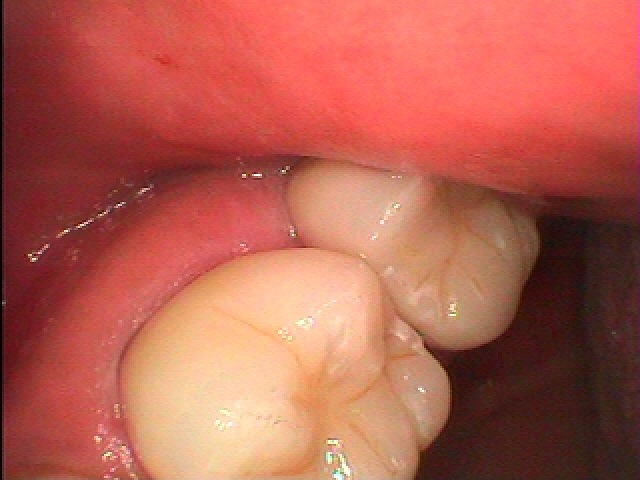

この7番の歯になります

大きく破折しています

3年間持ちましたが3年後に歯茎が腫れてきました

ここにて患者さんからも先生が言っていたインプラントを

との話になりました